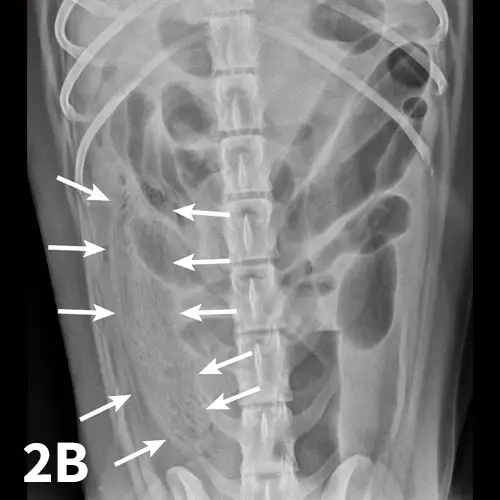

Radiographic features of small intestinal mechanical obstruction depend on its completeness, location, and duration.2 Whereas metallic FBs or those with mineral content are easily recognized within the GI lumen (Figure 1), nonmineralized, nonmetallic objects (eg, cloth) within the GI tract are more difficult to identify (Figure 2). Some may be recognized by their geometric shape. The most consistent sign of mechanical obstruction is variable dilation of intestinal loops proximal (orad) to the obstruction (described as a mixed population of small intestine; Figure 2). Determination of small intestinal diameter can be made by comparing it to the L5 vertebral body height in dogs.3 Values greater than 1.6 are suggestive of obstruction (Figure 2A). In cats, a ratio of the maximum small intestinal diameter to vertebral end plate height of L2 greater than 4 indicates a high likelihood of intestinal obstruction.4

A ventrodorsal abdominal radiograph showing a round metallic object in the small intestine.

FIGURE 1

VD abdominal radiograph of a 1-year-old cat with a 2-day history of vomiting and a nonobstructing metallic foreign body. A coin with a radiolucent center caused by erosion is present within the small intestinal loops in the right midabdomen. No dilated loops of small intestine are seen to indicate mechanical obstruction.